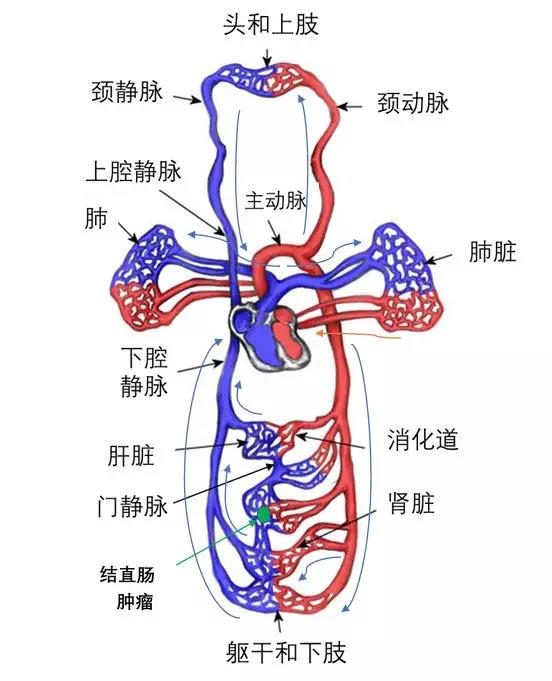

要回答这两个问题,我们先来了解一下结直肠肿瘤细胞在血管中流动情况。一些结直肠肿瘤细胞从原发病灶脱落,侵入血管,进入血流,这些细胞主要通过门静脉系统流入到肝脏,然后到达下腔静脉,同时也会有一些癌细胞通过阴部静脉或淋巴管路进入腔静脉,在此过程中,就有癌细胞留驻在肝脏,形成肝转移癌。

癌细胞从下腔静脉进入右心,并被输注到肺内,经过肺血管网络,一部分癌细胞留驻在肺内,形成结直肠癌肺转移癌。

从肺静脉回流到左心的血液,被射进主动脉,然后血液就快速地分布到全身,血液中的癌细胞,就被送往全身,并可能在体内某个部位或多个部位形成转移肿瘤,比如骨转移,脑转移,肾转移等。

经过四肢和躯干的血液,回流入静脉,并逐渐进入上、下腔静脉进入右心。

按照前面介绍的血流图,结直肠癌细胞进入血流,应该在门静脉中容易找到,或者转移到肺脏后,应该在病侧肺静脉内,容易找到CTC。真得会这样吗?